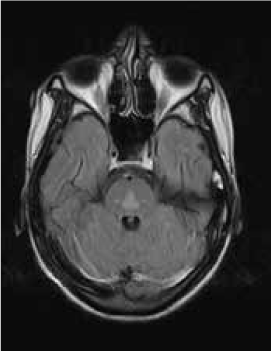

Magnetic resonance imaging (MRI) of the brain showed symmetrically increased T2-weighted and fluid-attenuated inversion recovery signal in the central pons (Figure 1) and in the striatum of the basal ganglia (Figure 2), with no contrast enhancement seen on corresponding T1-weighted postgadolinium images (Figures 3 and 4). Spinal MRI (Figure 5) demonstrated high signal on T2-weighted images from the area postrema in the medulla extending caudally to the T9 thoracic segment, with marked cord swelling and mild enhancement on T1-weighted postcontrast studies (Figure 6), in keeping with a longitudinally extensive inflammatory myelitis.

Magnetic resonance image of brain shows bilateral symmetrical high signal in caudate and lentiform nuclei on axial fluid-attenuated inversion recovery sequences

The clinical and radiologic features supported the diagnosis of NMO. However, the symmetrical pontine and basal ganglia high signal without contrast enhancement were considered to be strongly suggestive of concomitant ODS (pontine and extrapontine myelinolysis).

Neuromyelitis optica may lead to hyponatremia via at least two mechanisms. Area postrema involvement frequently causes intractable vomiting, and this may result in a low serum sodium level. Moreover, the syndrome of inappropriate antidiuretic hormone may develop in patients with NMO and hypothalamic lesions. In the present patient, the lowest recorded sodium level was 132 mmol/L. However, MRI demonstrated features of both central pontine and extrapontine myelinolysis, which, when occurring together, are considered virtually pathognomonic of ODS.4 Typical features include the symmetrical nature of the changes, the involvement of areas typically affected in ODS (pons, basal ganglia), and the sparing of peripheral pontine fibers. However, it remains a possibility that these radiologic changes were due to NMO primarily rather than osmotic demyelination. In a recent review, Kim et al.5 expanded on the range of MRI abnormalities consistent with NMO and NMO spectrum disorders. Gray matter demyelination of the thalamus and bilateral involvement of the corticospinal tracts have been described, although published examples are not as strikingly symmetrical as in this case and do not show the combination of central pontine demyelination with symmetrical striatal involvement.5 To our knowledge, these typical ODS changes in the context of NMO have been described in only one other case, in the Japanese literature.6